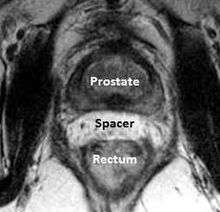

A new method to reduce rectal radiation injury in prostate cancer patients involves the use of an absorbable spacer placed between the prostate and rectum.

Such spacers are commercially available in some regions, and are undergoing clinical trials in others.[21] By temporarily altering the anatomy these products have the potential to allow for improved cancer targeting while minimizing risk to neighboring healthy tissues. Prostate Rectum Spacers should be compatible with all prostate cancer radiotherapy treatments including 3D conformal, IMRT and stereotactic radiation and brachytherapy.